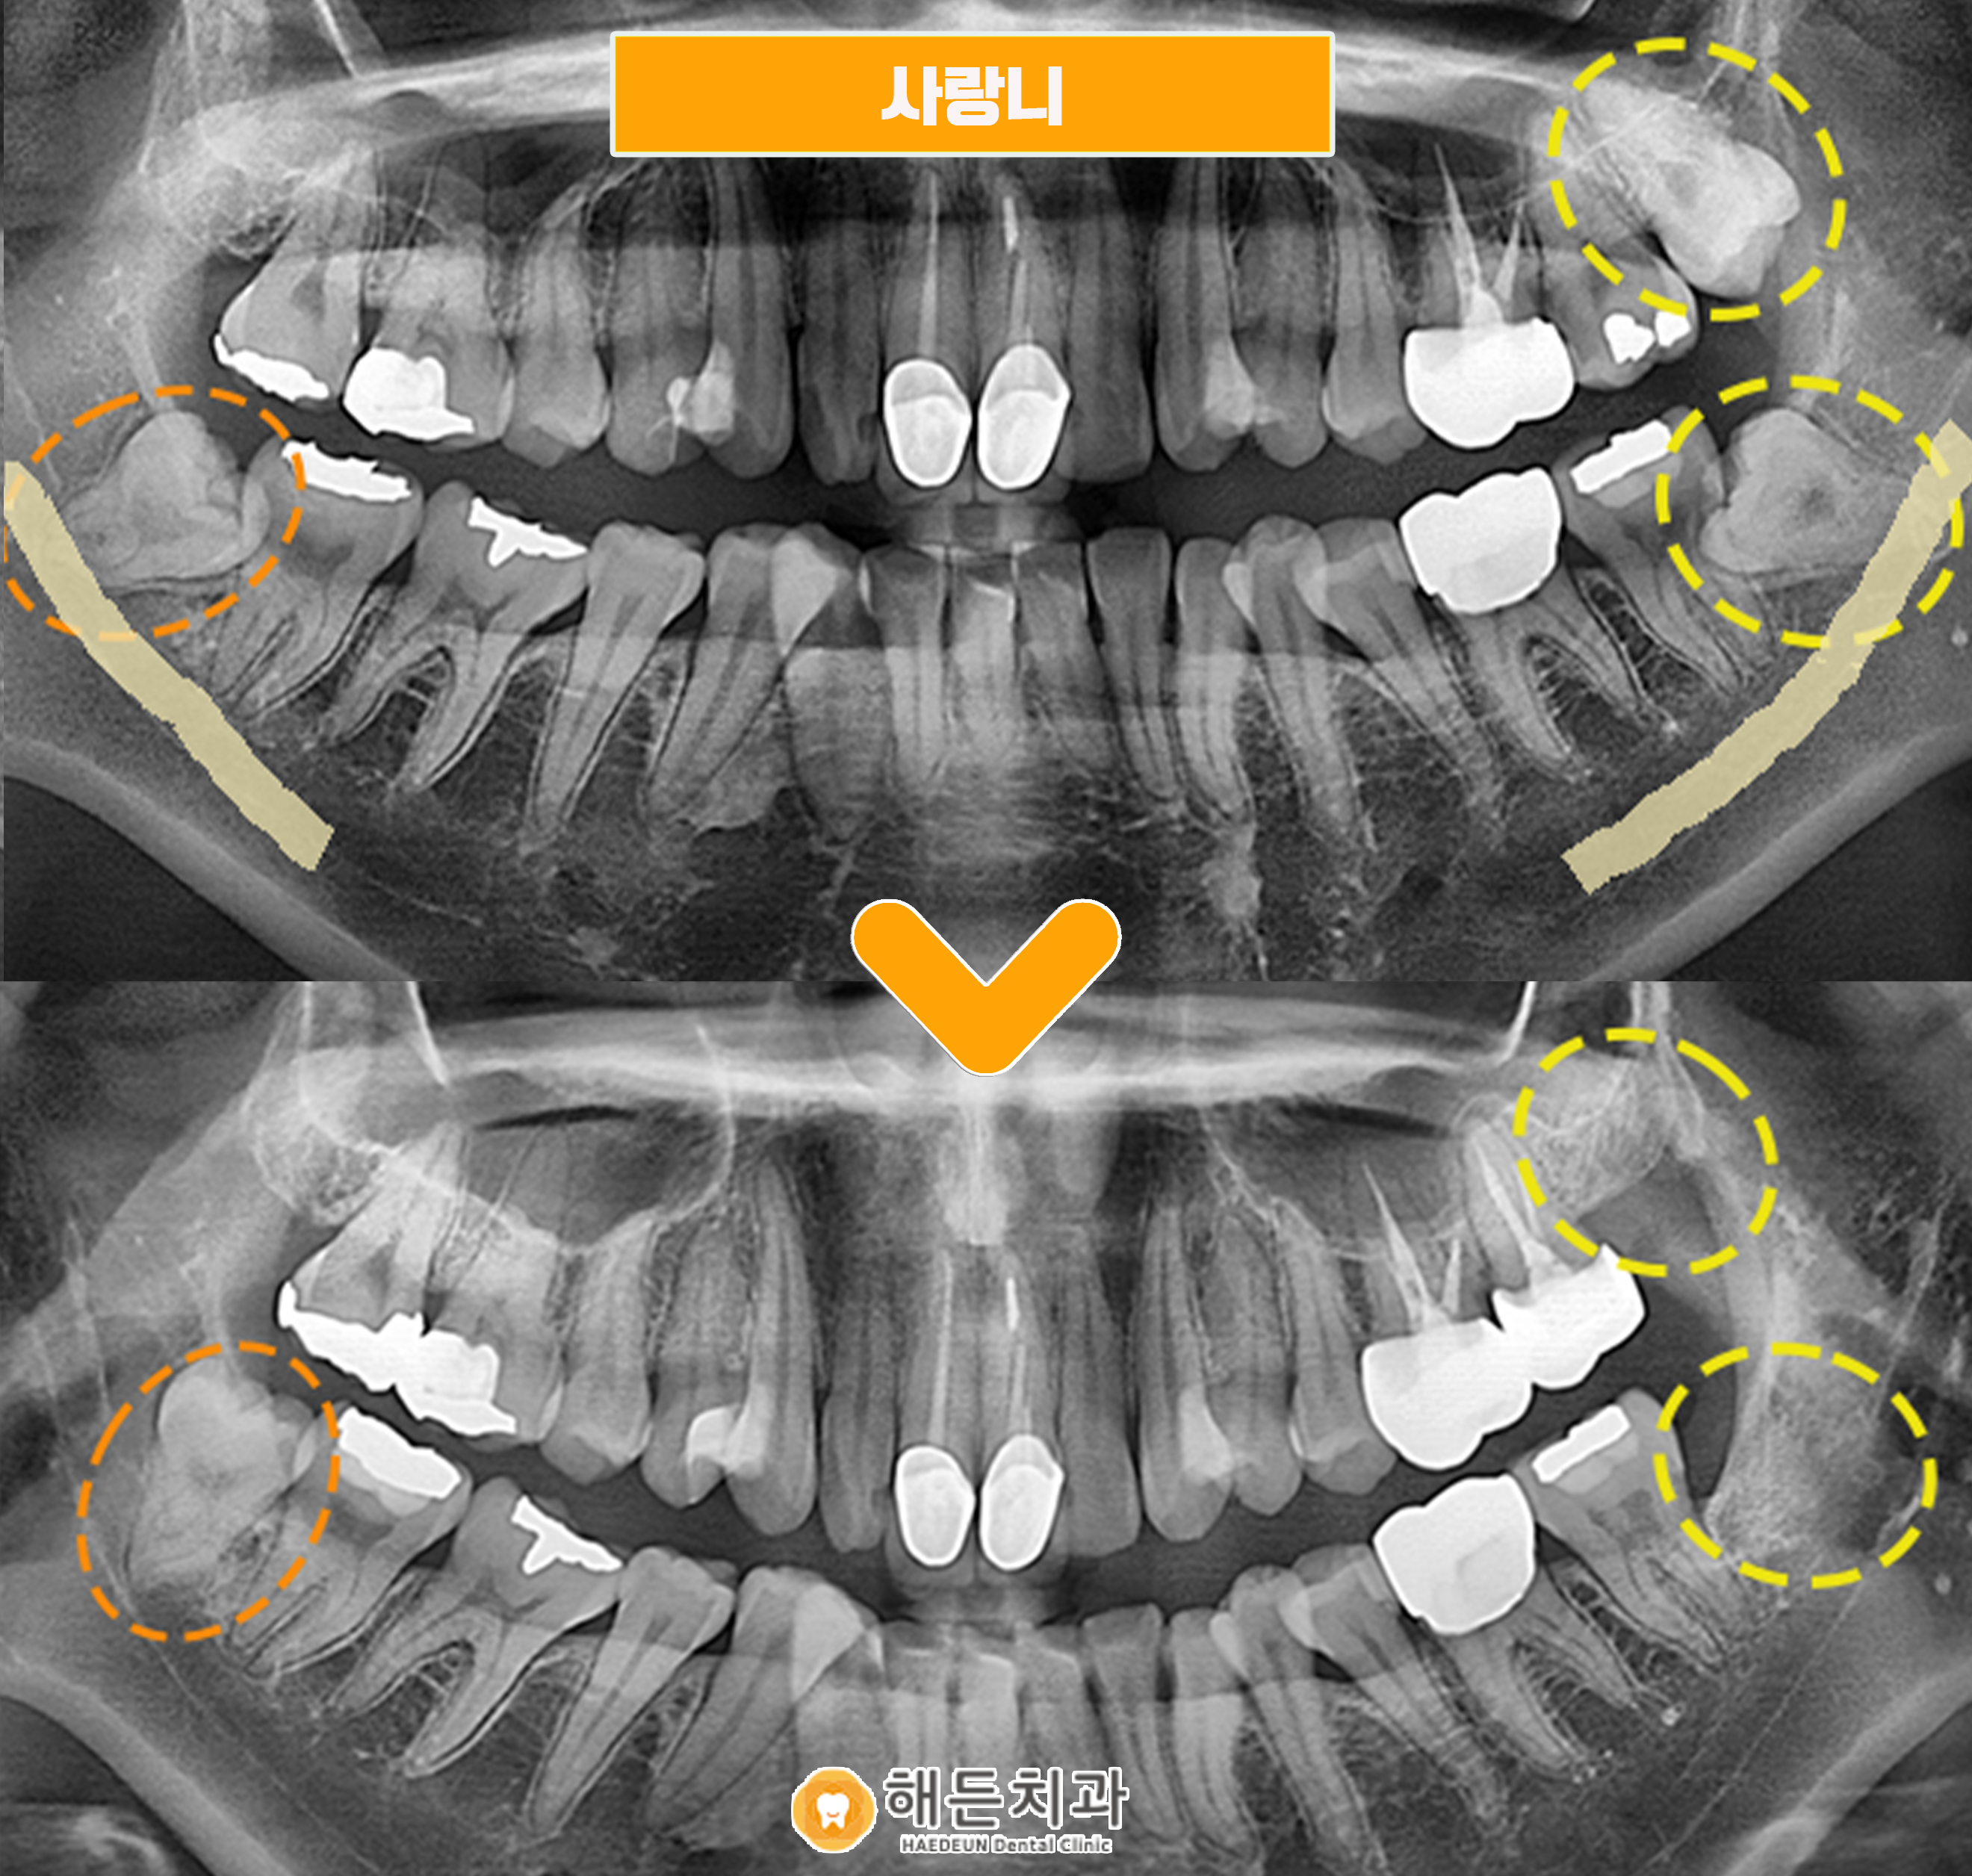

아래 환자분의 사례를 통해, 설명을 도와드리겠습니다.

위의 환자분께서는 사랑니 검진 및 발치를 위해 본원을 찾아주셨습니다.

정밀한 검진을 위해 파노라마 사진을 촬영해 확인해보니,

왼쪽 위아래와 오른쪽 아래 사랑니 총 3개의 사랑니를 관찰할 수 있었습니다.

위의 환자분께서는 양측 아래 사랑니는 매복이 되어 치아의 일부만 잇몸 위로 보이는 상태였습니다.

이렇게 일부가 매복되어 있는 사랑니는 양치관리가 어려워 충치 및 염증을 잘 유발시킬 수 있으며

인접한 앞의 치아에 좋지 않은 영향을 주기에 발치를 해주시는 것이 좋습니다.

우선은 왼쪽 위에도 사랑니가 있기 때문에, 왼쪽 위 아래 사랑니를 먼저 발치하고,

나중에 왼쪽이 다 아물고 나서

오른쪽 아래 사랑니에 불편감이 있는 경우, 발치를 도와드리기로 했습니다.

아래 사랑니가 아래턱에 지나는 하치조신경과 근접하게 위치해 있어, 주의하여 아산시사랑니발치를 도와드렸답니다.

사랑니가 신경관에 겹쳐 있는 경우엔 혹시라도 발치 과정에서 신경 손상이 일어나

입술이나 잇몸 감각에 이상이 생길 수 있는 위험성이 있으므로, 주의하여 발치를 진행하고 있습니다.